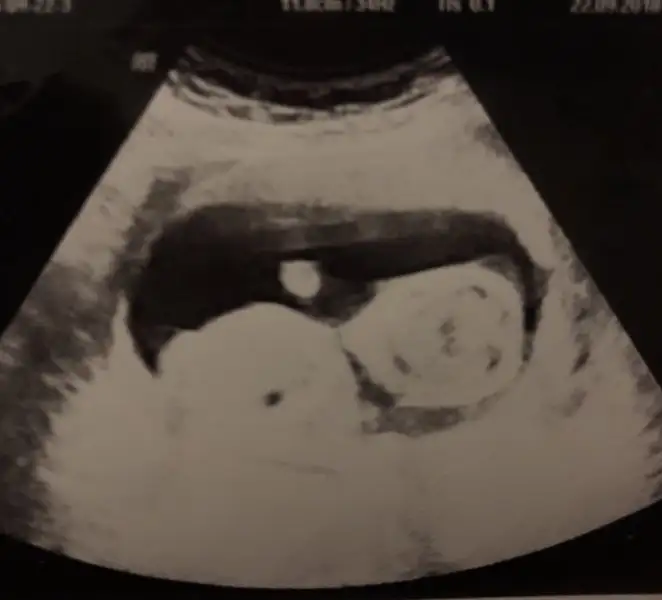

Bence de erkek canmUltrason resimleri bunlar

Ben göremiyorum tam olarak nereden anlaşılıyor oğlumda direk pipi görmüştik burada göremedimBence de erkek canm